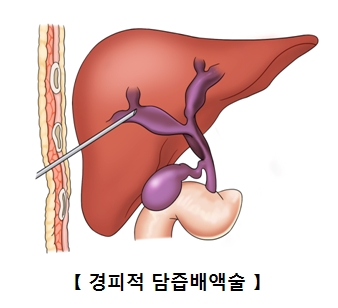

수술이 불가능한 환자 중 담도 폐쇄로 황달이 생긴 환자에게는 담도 스텐트 삽입술을 시행합니다. 이것이 불가능한 경우는 담즙이 배액되도록 하는 경피적 경간 담즙 배액술(PTBD)를 시행하여 황달을 완화시킬 수 있습니다.